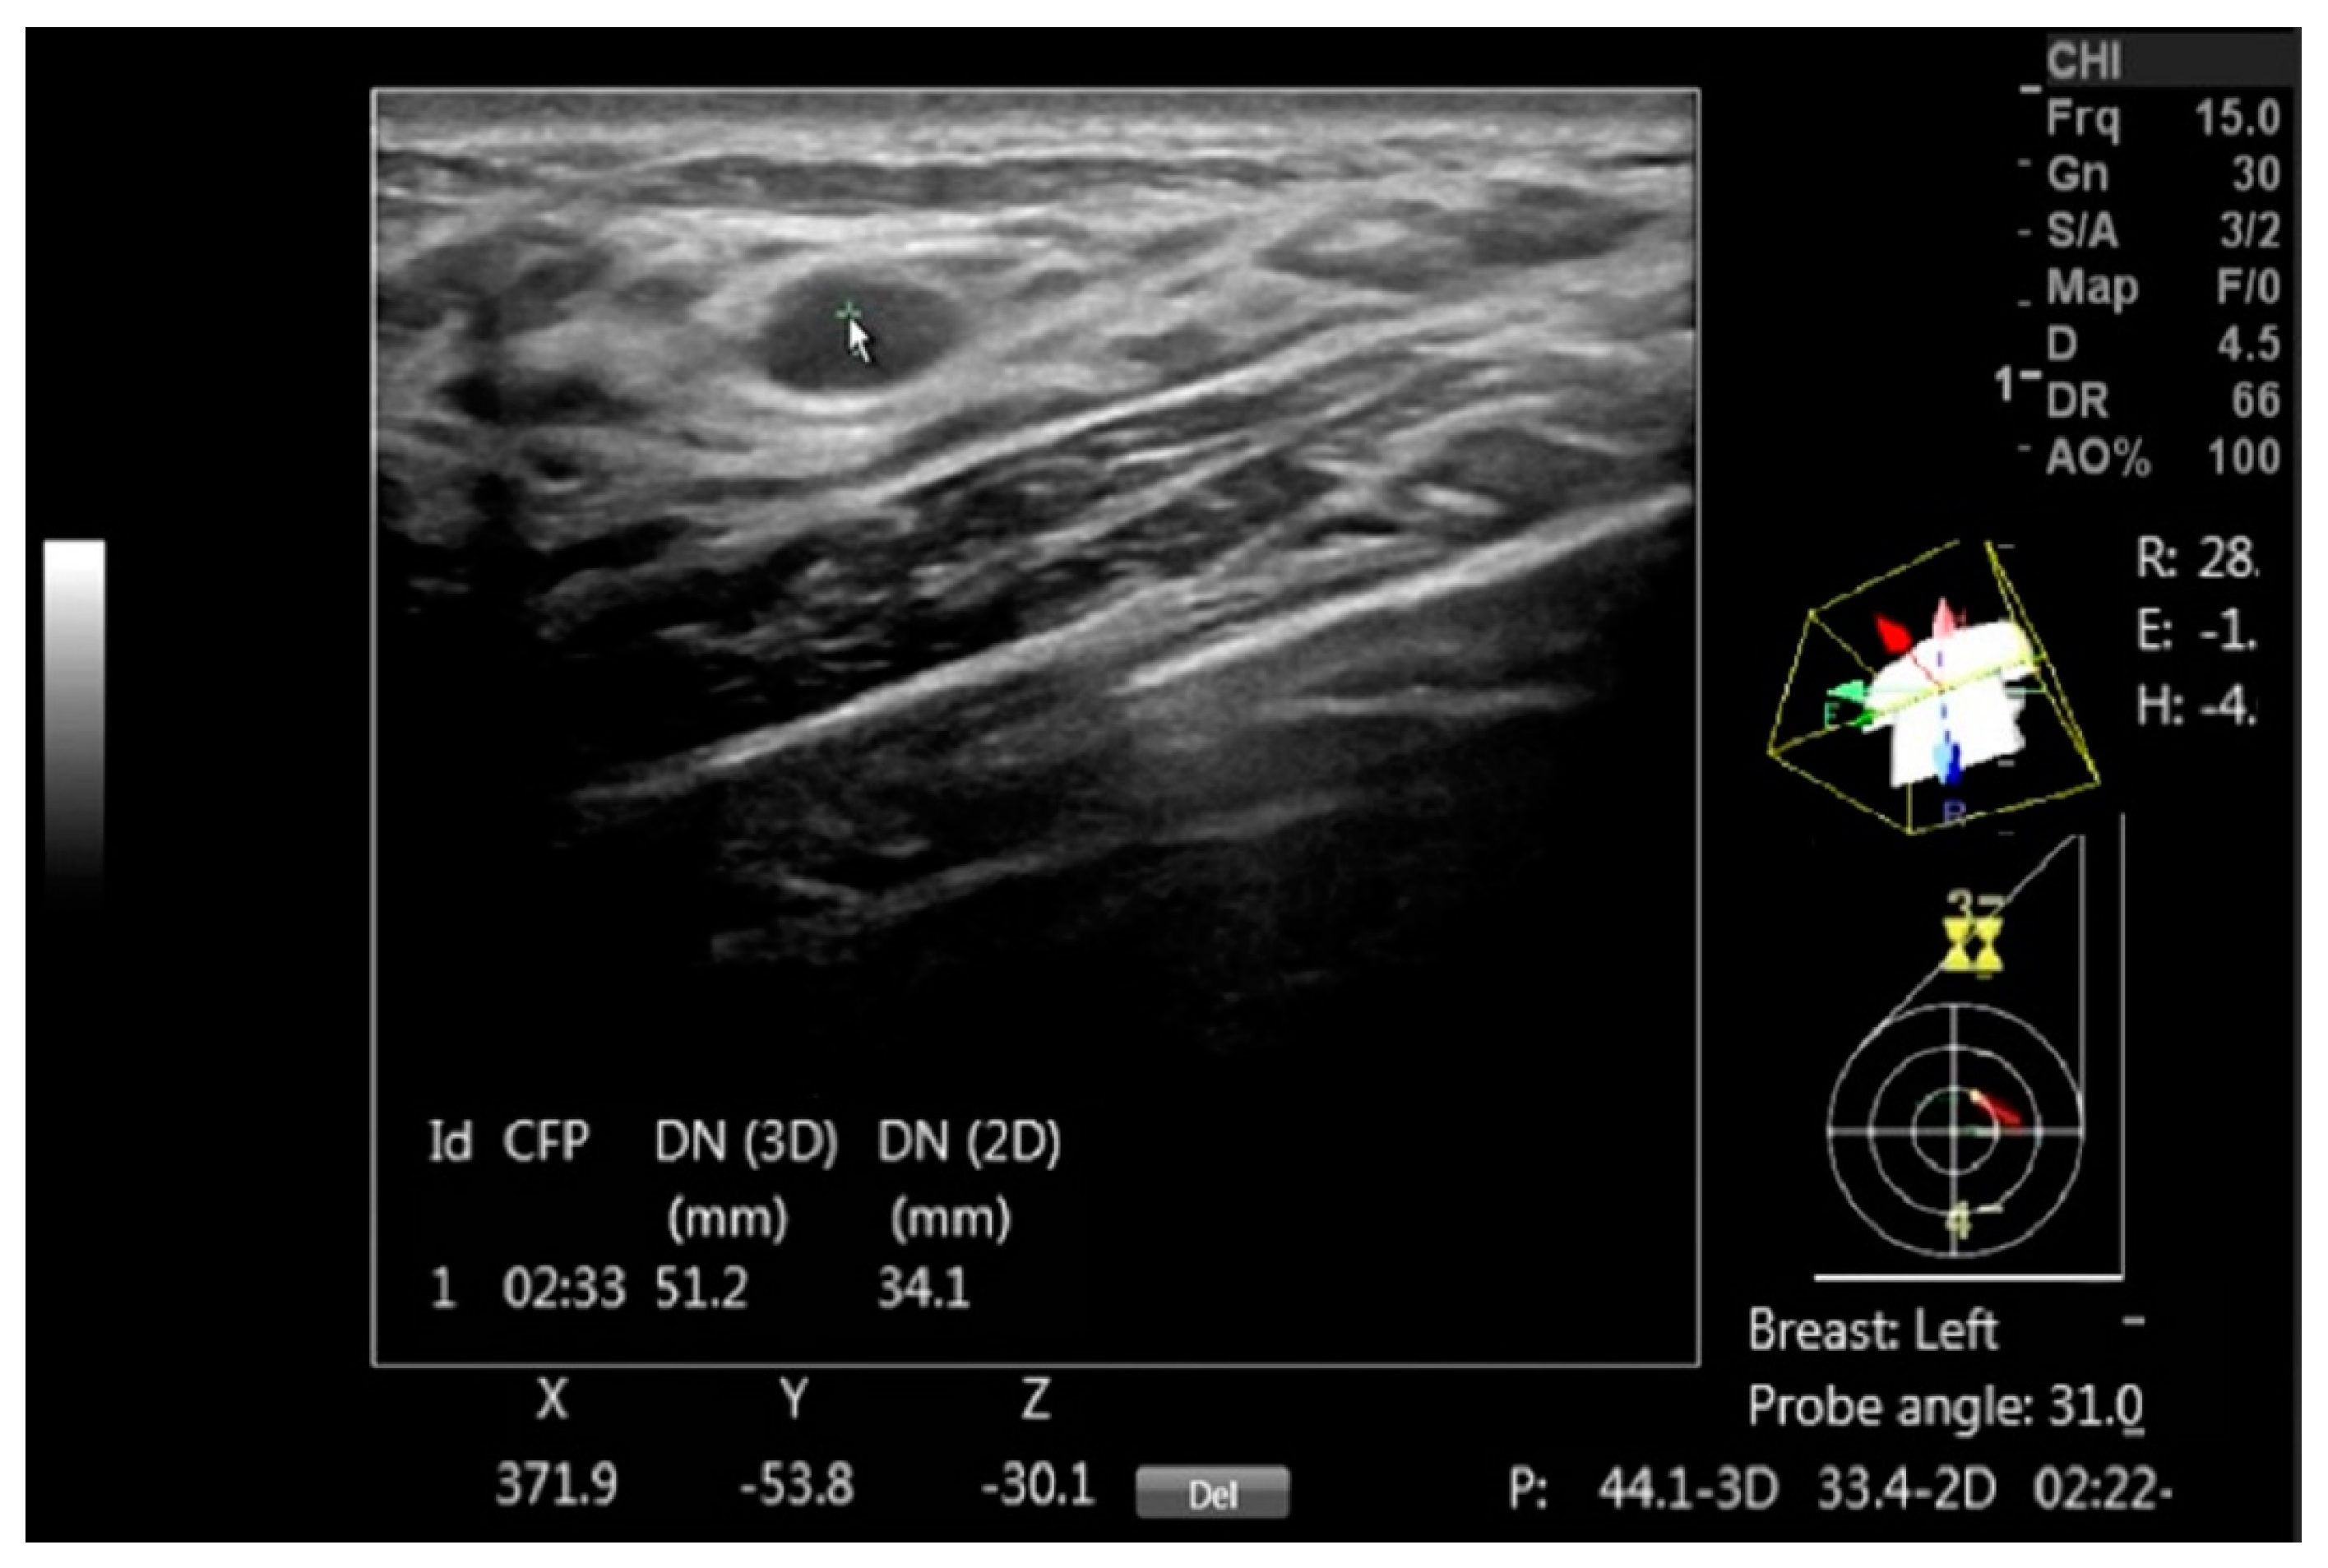

Figure 2.

A DICOM image with a benign mass is annotated using DEVICE to document the mass, with the arrow pointing to the mass. The on-screen information includes the clock face position (CFP), the 3D distance to the nipple (DN (3D)), its projection in the coronal plane (DN (2D)) and the Cartesian coordinates (X, Y, and Z) for each mass center point. Additionally, the display shows the probe head orientation over the diagram, the probe axis tilt in degrees and the body rotation relative to the exam table, which are marked as R, E and H and given in degrees.